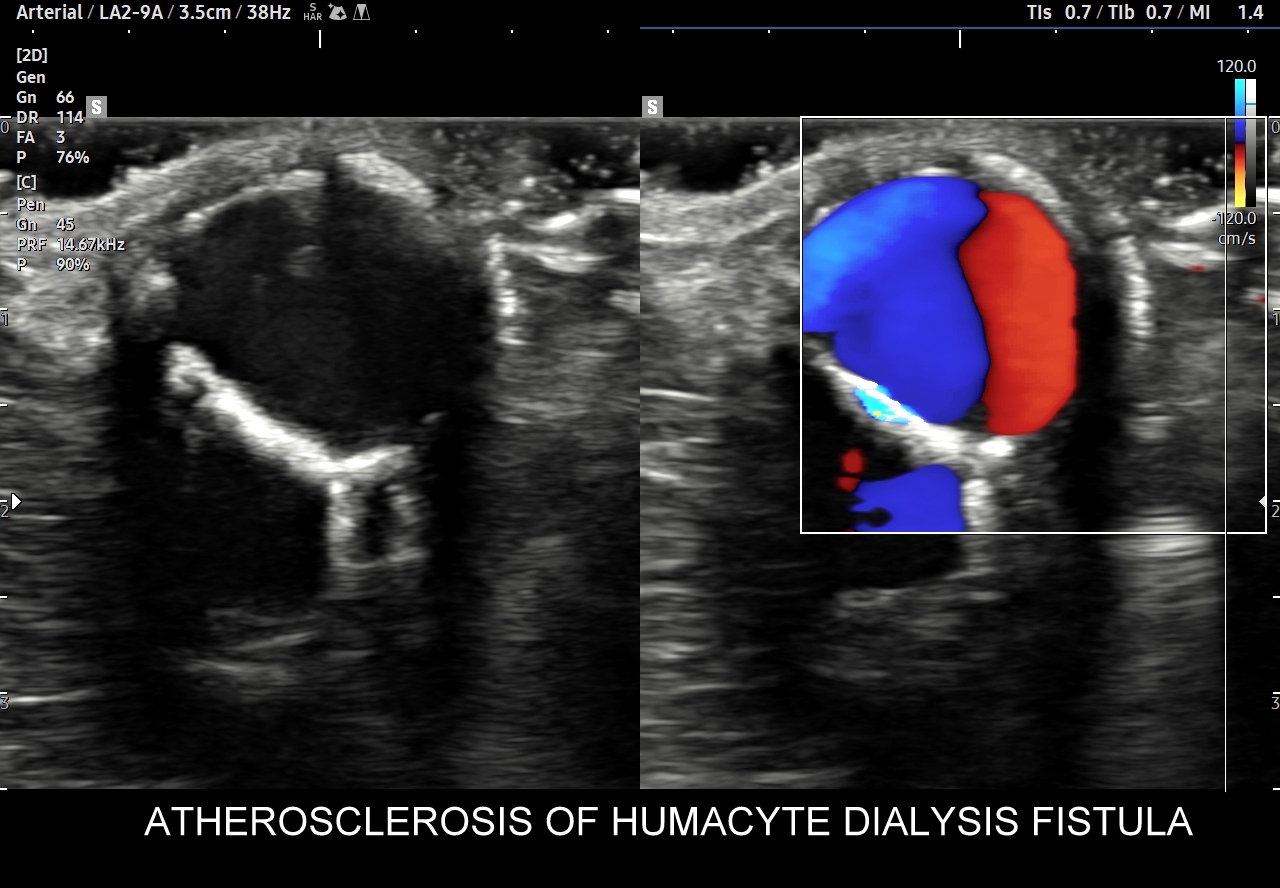

Na prezentowanych skanach przedstawiona jest ok. 7-letnia przetoka dializacyjna Humacyte od tętnicy ramiennej do żyły pachowej, która uległa zmianom degeneracyjnym w postaci rozwoju miażdżycy, dwóch tętniaków, skrzeplin przyściennych w jednym z tętniaków oraz dwóch zwężeń, w tym jedno na przebiegu naczynia a drugie na zespoleniu z żyłą. Pomimo wymienionych patologii przetoka zachowuje swoją funkcję, a jej objętość minutowa oszacowana w badaniu Doppler wynosi ok. 800 ml/min.

Następnie przechodzimy do oceny pierwszego zespolenia, tj. z tętnicą doprowadzającą oraz do skrupulatnego badania całego przebiegu przetoki z naczynia Humacyte. W trakcie badania wykryte zostały w/w nasilone zmiany miażdżycowo-kalcyfikacyjne, tętniaki oraz zwężenie w przebiegu naczynia. Proszę zwrócić uwagę, że opisane zmiany degeneracyjne są praktycznie podobne jak w typowej zaawansowanej arteriosklerozie tętnic widywanej często u pacjentów z nasiloną miażdżycą w przebiegu nikotynizmu, cukrzycy, czy nadciśnienia tętniczego.